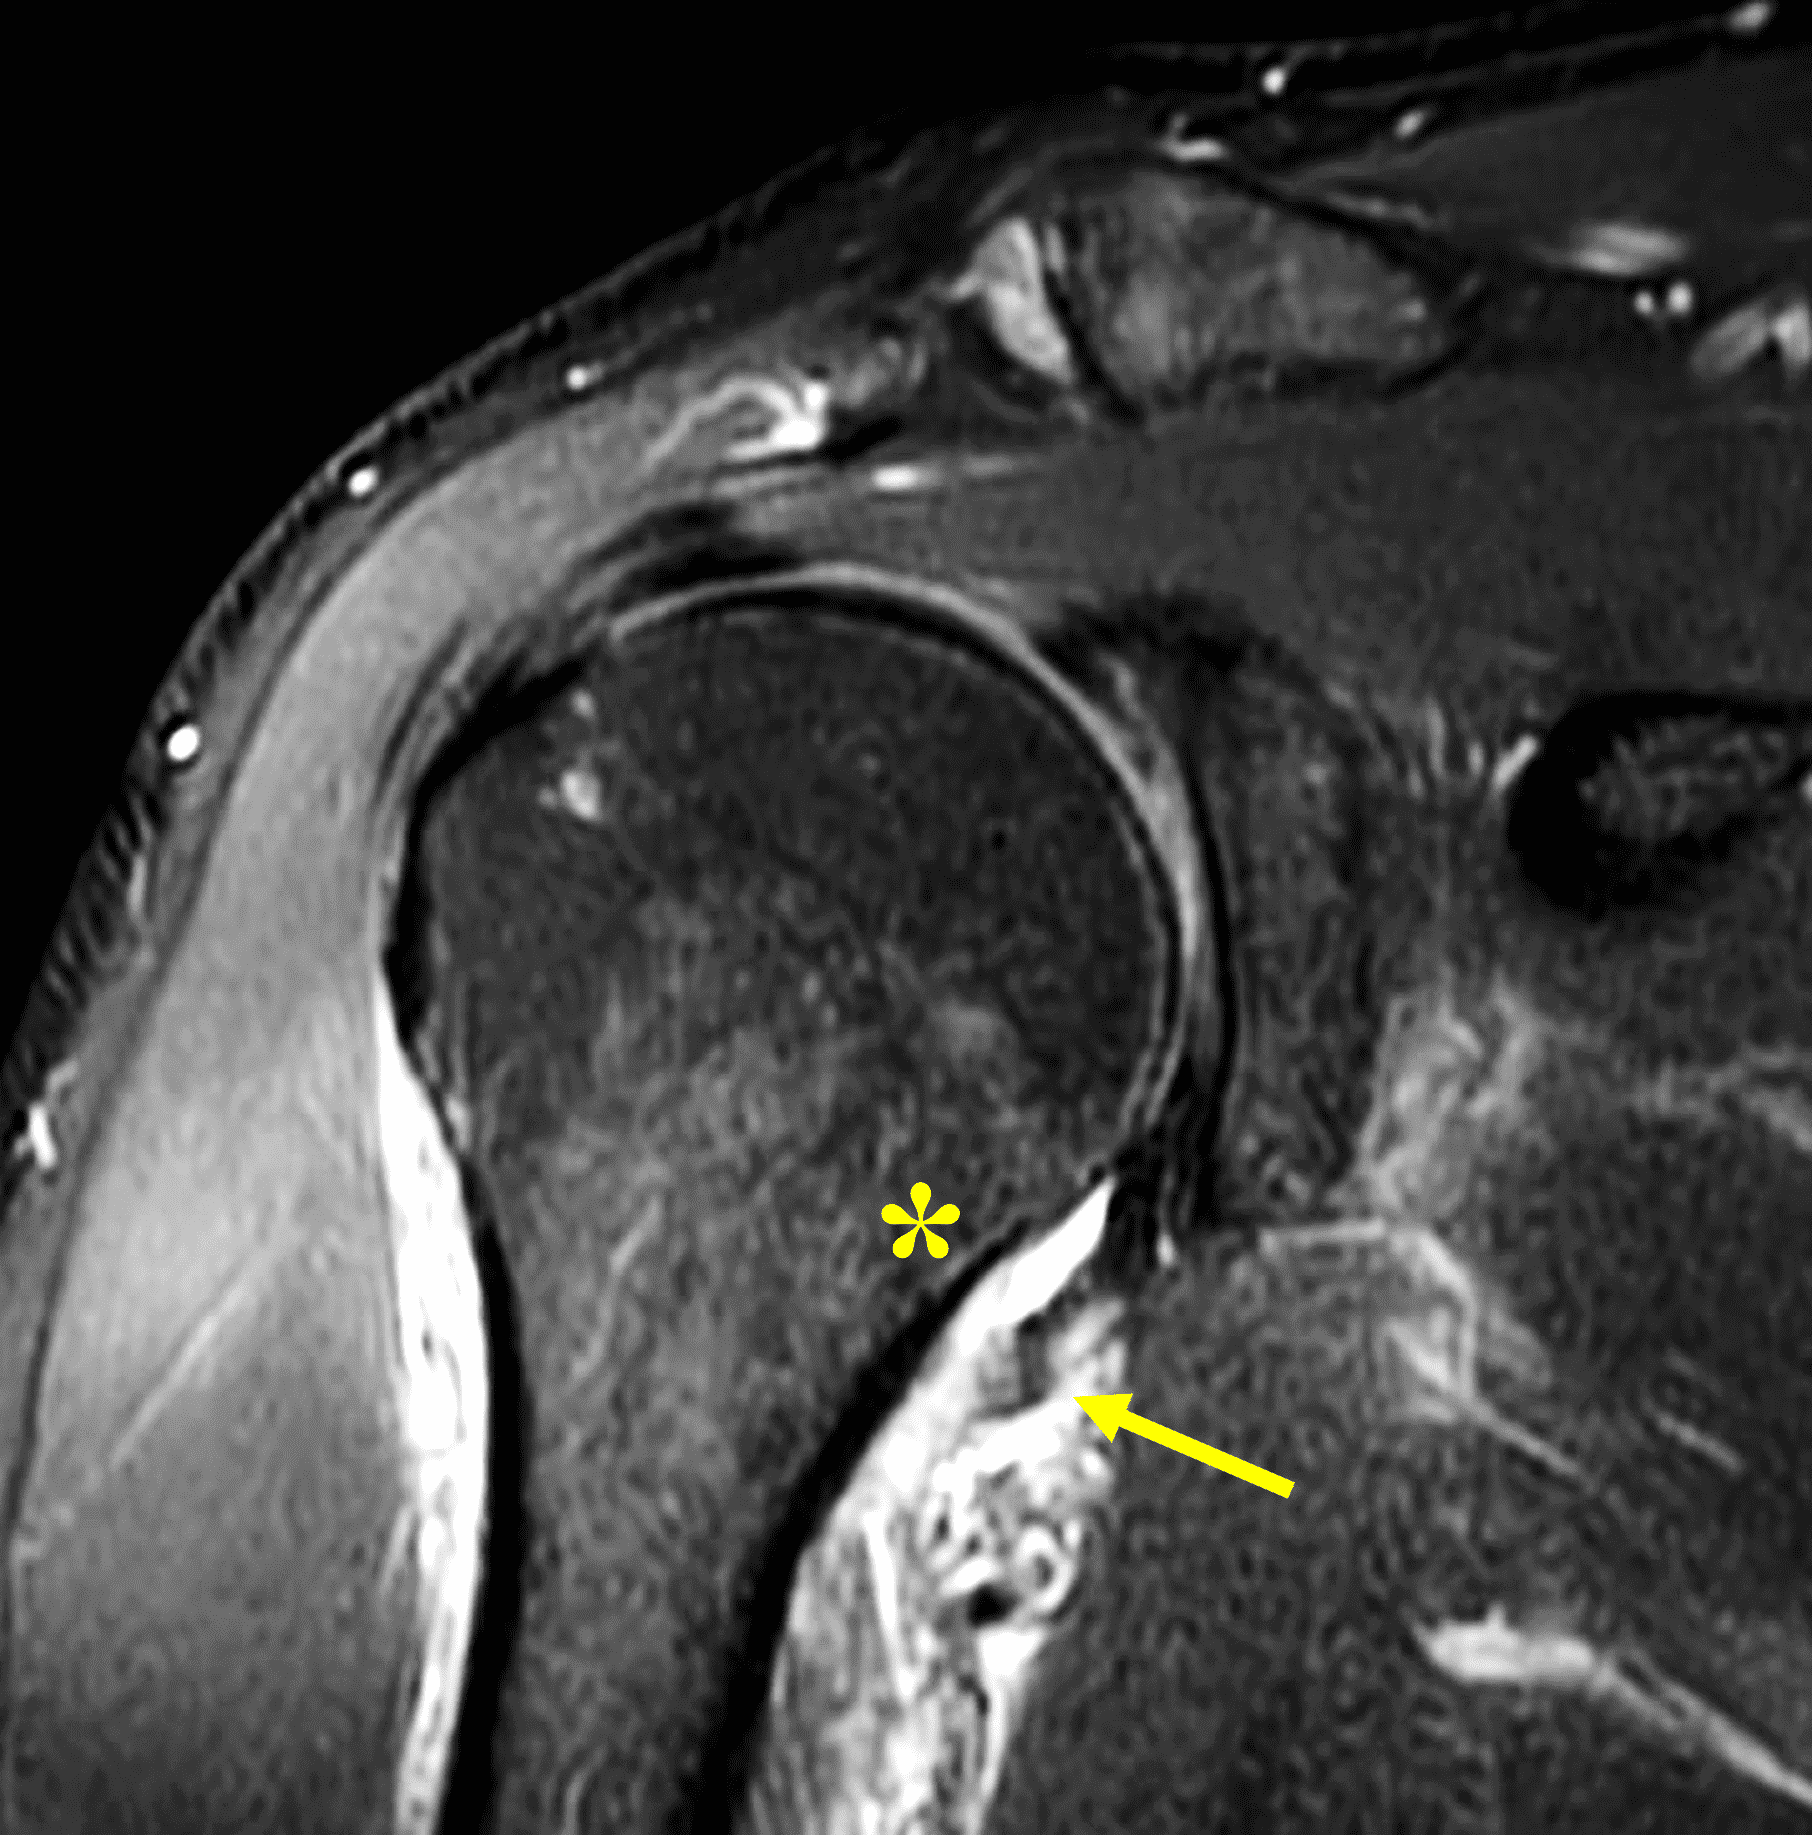

Figure 2: (2A) An axial image at the level of the humeral lesser tuberosity (LT) shows an intact subscapularis tendon (arrowheads). (2B) More inferiorly at the level of the humeral neck (HN), the direct muscular attachment of subscapularis (yellow arrows) is avulsed from the humerus together with the anterior band of the inferior glenohumeral ligament (red arrow), representing humeral avulsion of the glenohumeral ligament, a HAGL lesion. (2C) A coronal image through the anterior humerus shows the avulsed direct muscular attachment of subscapularis (yellow arrows), and the retracted end of the torn anterior band of the inferior glenohumeral ligament (red arrow). (2D) The radiograph shows a small, avulsed bone fragment of the humerus (red arrow), making this injury a “bony” HAGL (BHAGL) lesion. He failed 3 weeks of conservative management, with persistent 7/10 shoulder pain and was managed operatively with a lesser tuberosity repair. 6 months later, after taking a hiatus from baseball, his pain was completely resolved.

A pattern of injury has recently been described in pitchers and forceful ball throwers, who can injure the inferior subscapularis with sparing of the upper subscapularis muscle and tendon, like in the test case (Figures 1 and 2).20 A retrospective review of MRI scans from a Major League Baseball organization over a 5 year period identified 11 of 133 MRIs with subscapularis injury, 10 of which showed injuries occurring in the inferior half of subscapularis at the myotendinous junction, with sparing of the tendon.21 These inferior myotendinous injuries can extend to involve the direct muscular attachment at the humerus.

On MRI, injuries to the direct muscular attachment can manifest with edema and hemorrhage within the muscle and surrounding soft tissues, and/or avulsion of the muscle from the humerus. The lower signal intensity of the anterior band of the IGHL allows it to be distinguished from the direct muscular attachment of subscapularis, which can be important if the anterior band is torn and retracted (Figure 18). In these cases, the muscle tissue should not be mistaken for an intact IGHL. Hematomas may occur with injuries of the direct muscular attachment and can become quite large as they expand within the axillary soft tissues (Figure 19).